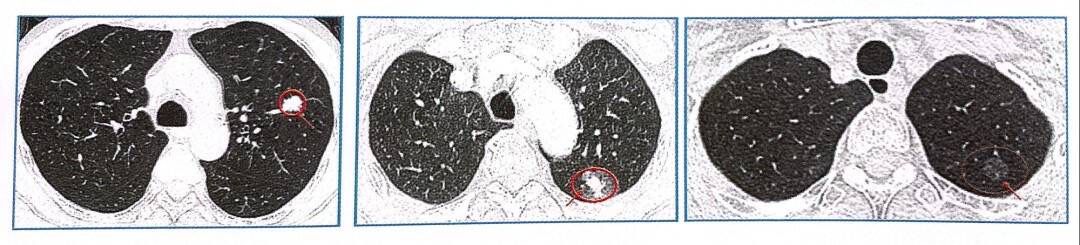

肺结节分为实性结节、纯磨玻璃结节和混合磨玻璃结节三种类型。其中混合磨玻璃结节恶性程度最高。

(左)实性结节、(中)混合磨玻璃结节、(右)纯磨玻璃结节